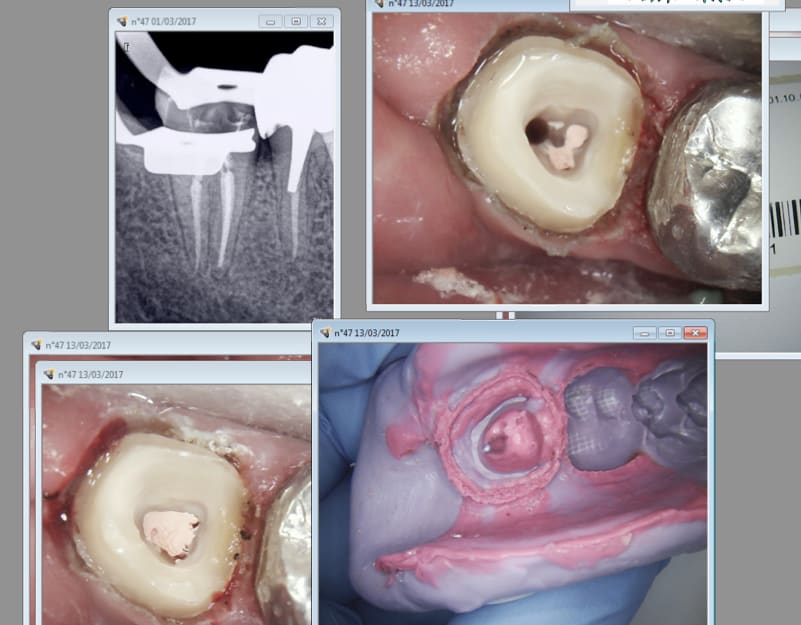

47

Capture d écran 2017 03 13 14.39 - Eugenol

Ca marche bien le laser. Les empreintes injectées aussi d'ailleurs ! -)))

Mon prothésiste va penser que j'ai pété un plomb. Il sera pas loin de la vérité d'ailleurs. -)))

Pour le seul ic à clavette depuis des années j'ai pas fait les choses à moitié ! -)))